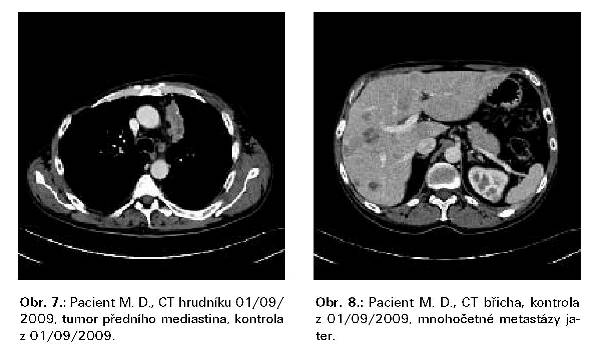

Mírná progrese i v únoru 2009. V 05/2009 mírná regrese plicních

ložisek, nekrotické změny v jaterních ložiscích zřejmě v

souvislosti s léčbou. Grafy ukazují dynamiku onkomarkerů.

V 05/2009 karcinoidová krize, otok obličeje,

flush, hypotenze, zvládnuto volumoresuscitací, i.v. octreotidem. Od

09/2009 stav stacionární. [OBR. 7, OBR. 8]